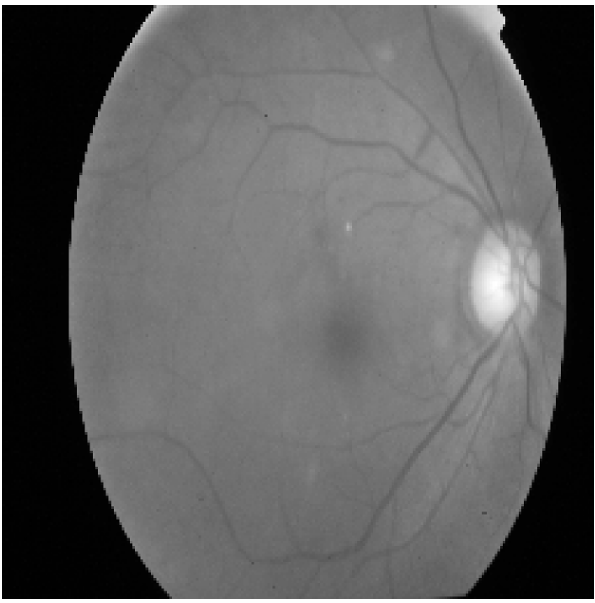

Refer to caption

(a)

(b)

(c)

Figure 4: Illustration of the preprocessing pipeline applied to a fundus image. From left to right: (a) Original color image, (b) grayscale conversion used for HOG computation, and (c) corresponding Histogram of Oriented Gradients (HOG) visualization highlighting edge and texture features.